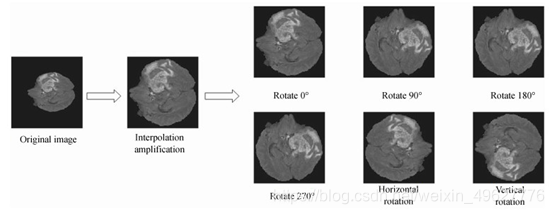

由于医学图像获取来源有限,因此在现有数据集的基础之上进行样本增广.首先将尺寸为240×240的图片进行裁剪,只保留含有脑部的区域,去除周围的“0”值像素点;然后再采用最邻近插值法[19]对去除背景后脑部图像进行放大,凸显脑部影像特征;最后对处理后的样本进行旋转和镜像翻转.脑肿瘤样本增广方法示意图如图 6所示.